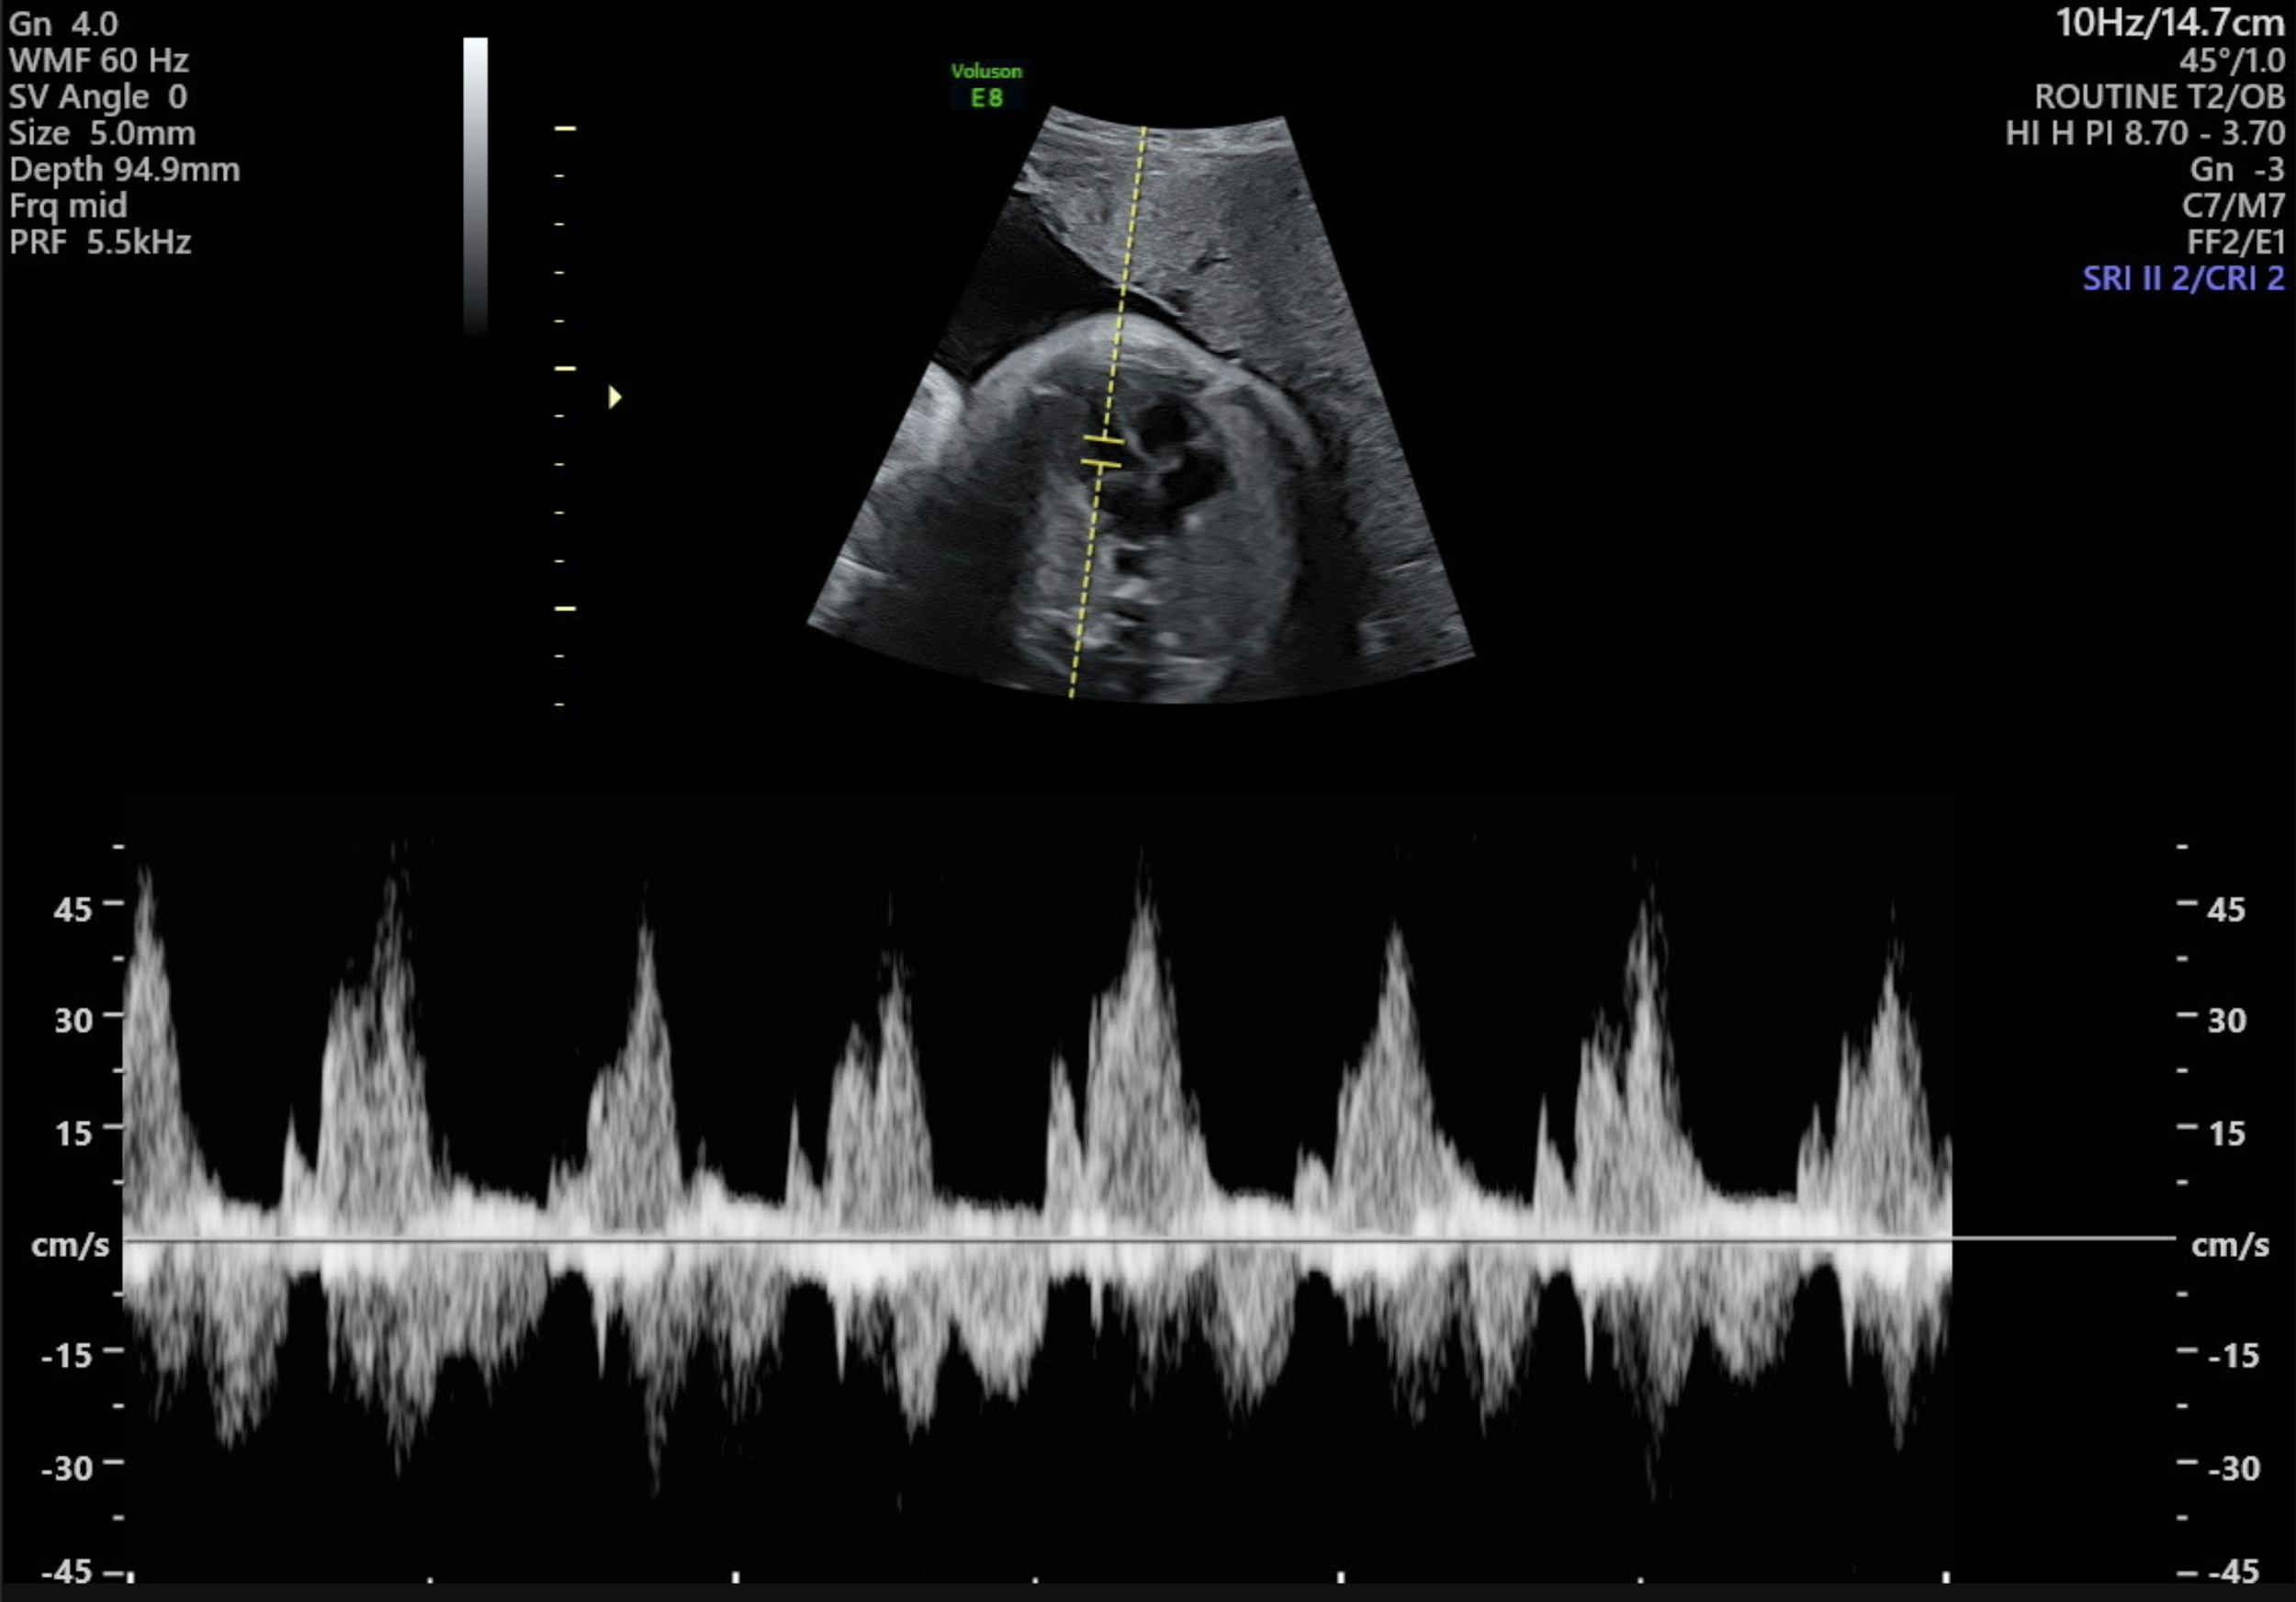

- Blood flow in the fetal brain (middle cerebral artery), umbilical cord (umbilical artery) and/or ductus venous when indicated.